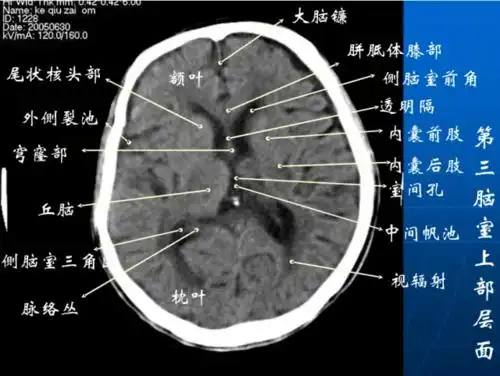

影像医生必须掌握的头颅ct解剖与常见出血梗死判读